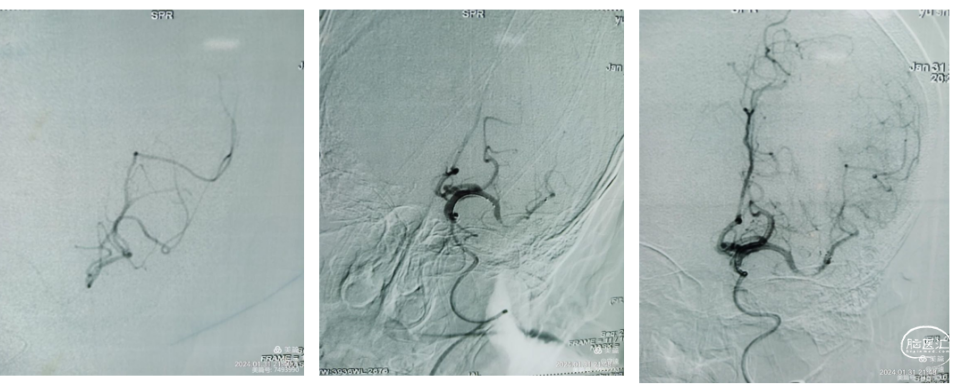

130cmSIM2导管辅助6FGMAX长鞘同轴建立通路。将泥鳅导丝携带130cmSIM2造影导管超选颈总动脉,跟进SIM2导管到达颈总动脉远端、同轴将6FGMAX长鞘到达颈内动脉起始部,建立血管通路。

泥鳅导丝内芯支撑输送中间导管。通过GMAX长鞘,6F中间导管内通过C1段V型迂曲到达C1远端。泥鳅导丝在中间导管内不出头,中间导管边前行边跟进泥鳅导丝,中间导管到达C6段环状迂曲部位不能通过迂曲血管。

微导丝顺利到达M2段,但微导管通过艰涩,考虑狭窄明显。微导管到达M2后冒烟远端血管显影良好。释放4*20mm Solitaire™支架后推注替罗非班,保持10-15分钟造影血流显影,但狭窄明显。取栓一次后见M1远端狭窄明显.

再次将支架置于M1远端,在支架铆定下跟进中间导管越过了C6迂曲到达M1段,抽拉结合2次取栓。通过中间导管进行二次抽吸后造影显示:血管再通,M1远端仍有小节段狭窄,但血流达到3级。结束手术。